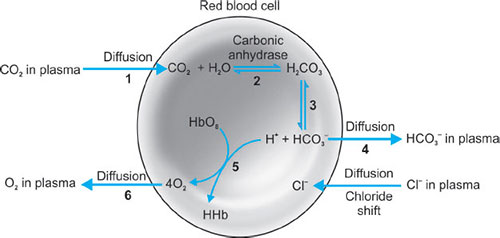

The Bohr effect: This describes the affect that CO2 has on influencing the release of oxygen to the tissues. On entering red blood cells the following reaction occurs:

CO2 + H2O ↔ H2CO3 ↔ H+ + HCO3−

An increase in H+ will cause an acidosis and therefore encourage the release of oxygen from Hb.

In the lungs where the CO2 is being removed, the alkalosis will encourage the uptake of oxygen.

The Hamburger effect (chloride shift) (Fig. 36).

The transport of chloride ions into the cell as a result of outwards diffusion of bicarbonate in order to maintain electrical neutrality.

The Haldane effect:

This phenomenon refers to the increased ability of blood to carry CO2 when hemoglobin is deoxygenated. Deoxyhemoglobin is 3.5 times more effective than oxyhemoglobin in forming carbamino compounds.